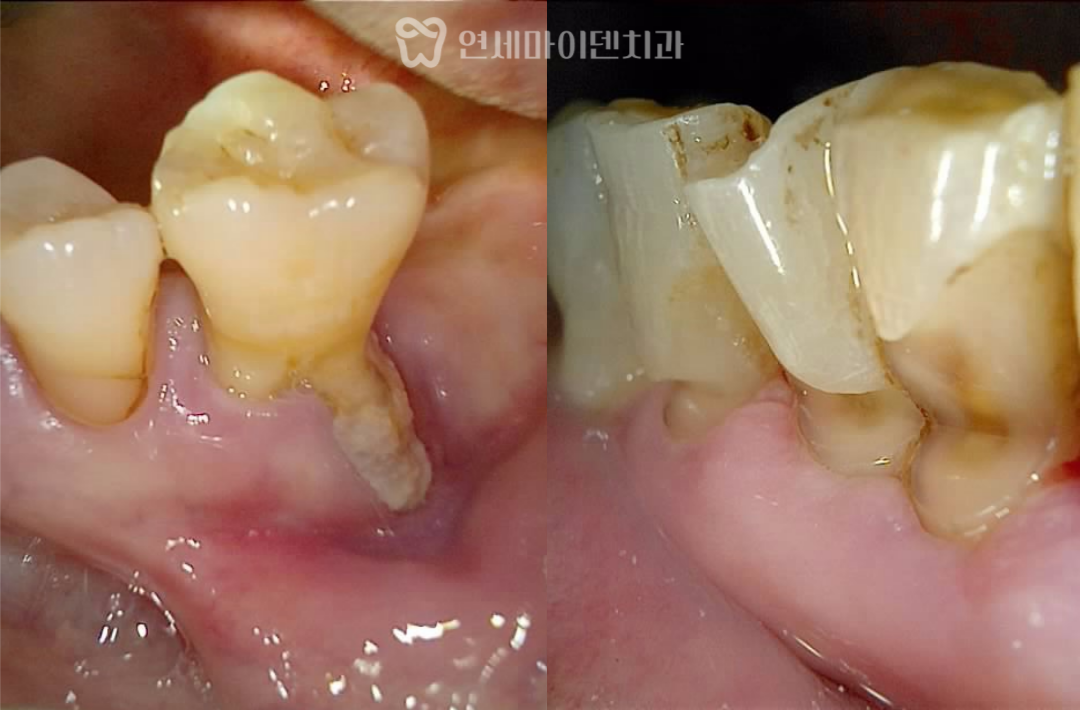

경과 관찰 후 보철 연결

수술 후에는 잇몸 회복 상태를

지속적으로 확인했습니다.

염증의 원인이 제거되면

잇몸은 비교적 빠르게 안정되는 경우가 많습니다.

약 3개월의 치유 기간을 거친 뒤

상부 구조를 연결하고

맞춤형 지대주를 형성한 후

보철을 완성했습니다.

이 시점부터 해당 부위로 식사가 가능해졌고

환자분의 생활 불편이 크게 줄었습니다.

이후 잇몸 회복을 확인하면서

보철까지 마무리했고

양쪽 어금니로 균형 있게

식사가 가능한 상태를 목표로 치료를 진행했습니다.